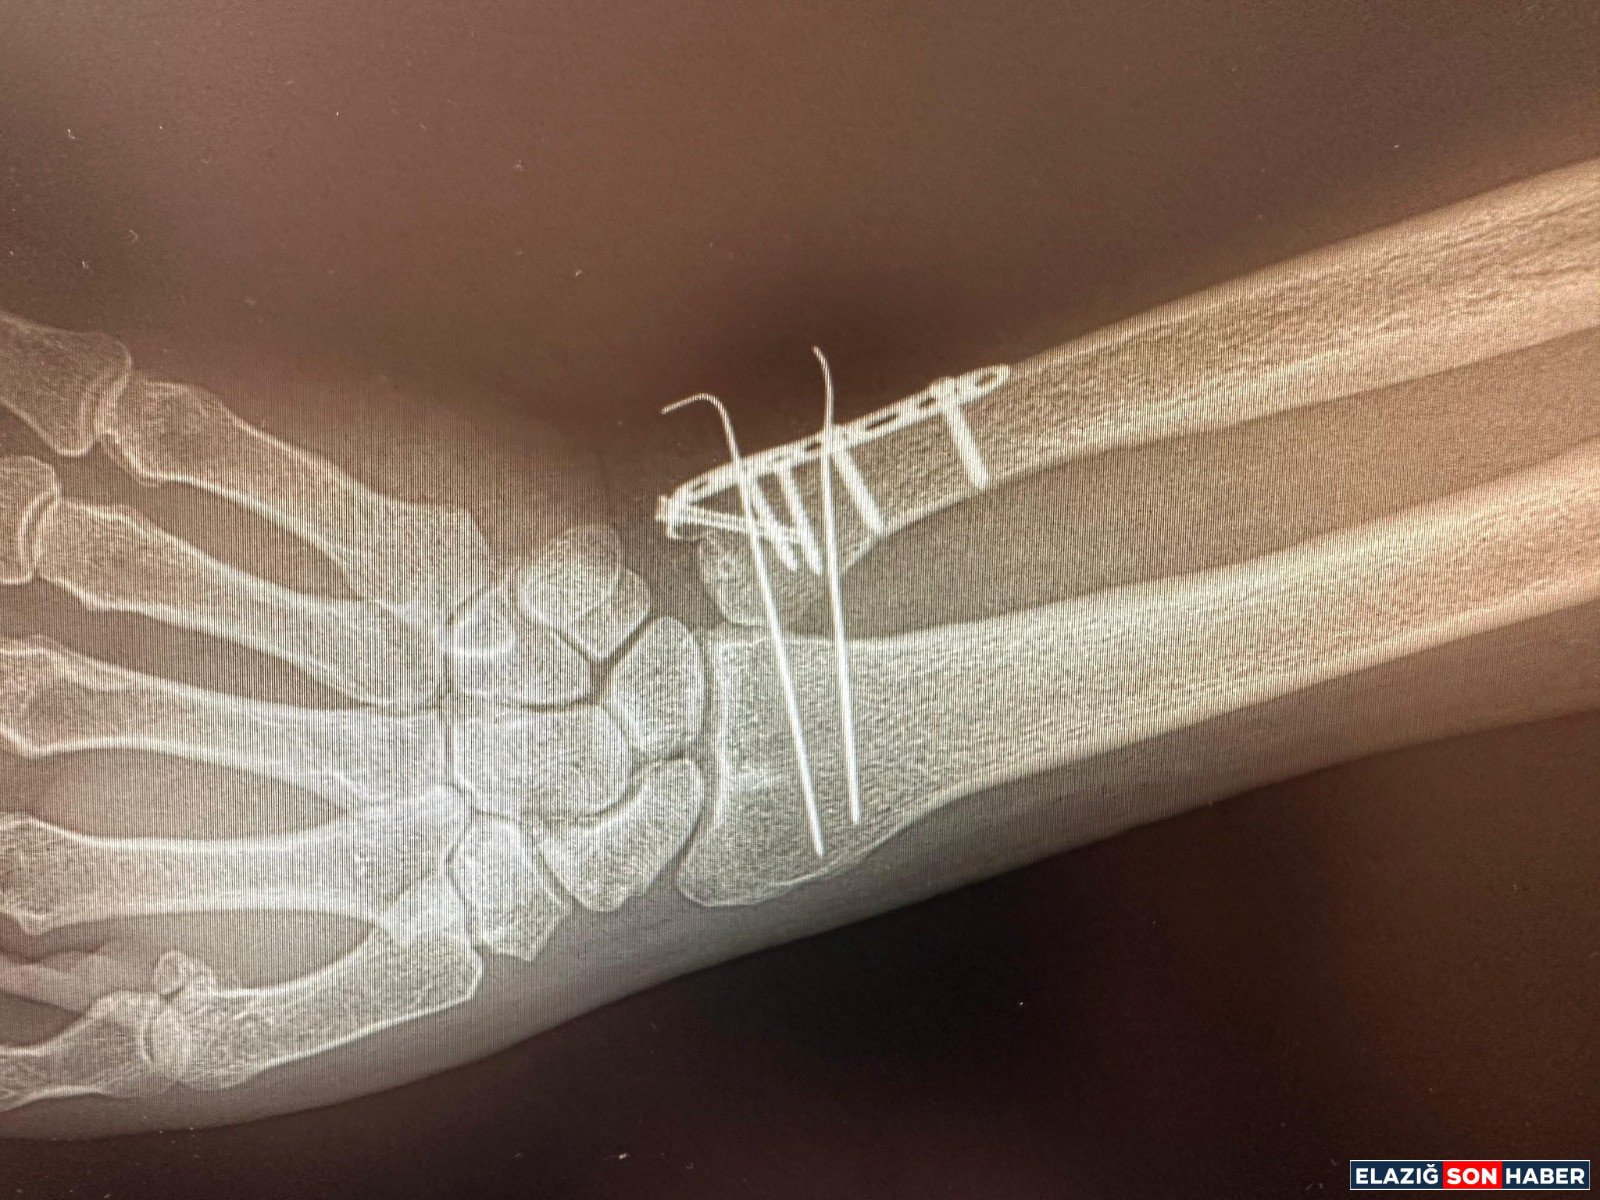

C Kollu Skopi (C-arm); ameliyathane ortamında hastanın iç yapısını anlık ve hareketli olarak görüntüleyen, X-ray tabanlı taşınabilir bir röntgen cihazı olarak biliniyor. C şeklindeki yapısı sayesinde her açıdan görüntü alabilen cihaz; özellikle ortopedi, travmatoloji, beyin cerrahisi, üroloji ve kardiyoloji işlemlerinde yüksek çözünürlüklü görüntü sağlayarak müdahalelerin daha güvenli ve hızlı yapılmasına imkân tanıyor.

• Kırıkların düzeltilmesi

• Vida ve plak uygulamaları